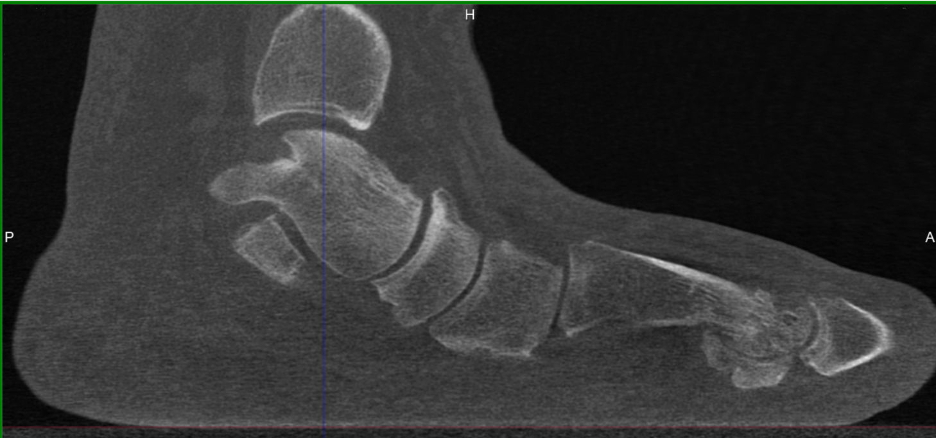

Indeed, authors have demonstrated evidence of acquired sagittal plane instability of the first TMT in HAV patients using various techniques. Weight-bearing radiographs reveal plantar gapping and dorsal translation of the first TMT joint.28 These findings have been replicated in simulated weight-bearing computed tomography (CT) imaging studies as well as true weight-bearing CT (WBCT) studies that show plantar gapping and dorsal translation of the first metatarsal at the first TMT joint in HAV patients (Figures 1A,B).29-30

In terms of joint rotation, the first TMT joint moves in the direction of supination, not pronation in patient with HAV. Three studies using standard CT imaging compared joint positions of the medial column of the feet in both an unloaded and loaded condition. The studies compared these joint rotations in patients with HAV deformity and healthy control patients. Geng and colleagues observed that the first metatarsal moved in the direction of inversion, dorsiflexion and adduction relative to the medial cuneiform and the magnitude of this motion was greater in all 3 planes in the patients with HAV deformity.29 Watanabe found that both HAV patients and controls demonstrated equal magnitude of 5 degrees eversion of the navicular with loading of the foot, while the HAV patients demonstrated greater inversion (2 degrees) of the first metatarsal relative to the medial cuneiform than controls.45 There was minimal coronal plane rotation of the cuneiform in both groups. Kimura and colleagues found that the talonavicular joint rotated in the direction of eversion, with greater magnitude and variability in the HV group.46 At the first naviculocuneiform joint, the HAV patients showed eversion at a magnitude of only 0.2 degrees while control patients showed mild 1.5 degrees inversion. At the first TMT joint 4.9 degrees inversion occurred in the first metatarsal with loading of the foot. In addition, dorsal hypermobility of the first ray was present in patients with HAV deformity who exhibited more dorsiflexion at the first TMT joint than healthy controls. The overall net frontal plane motion of the medial column was in the direction of eversion, primarily due to motion of the navicular on the talus. Pronation motion of the navicular measured 9.6 degrees, which offset 4.9 degrees of supination motion of the first metatarsal at the first TMT joint. Therefore, when the entire foot pronates, the net pronation or eversion of the joints proximal to the first TMT articulation can ultimately place the first metatarsal everted to the ground (Figures 2A-E).